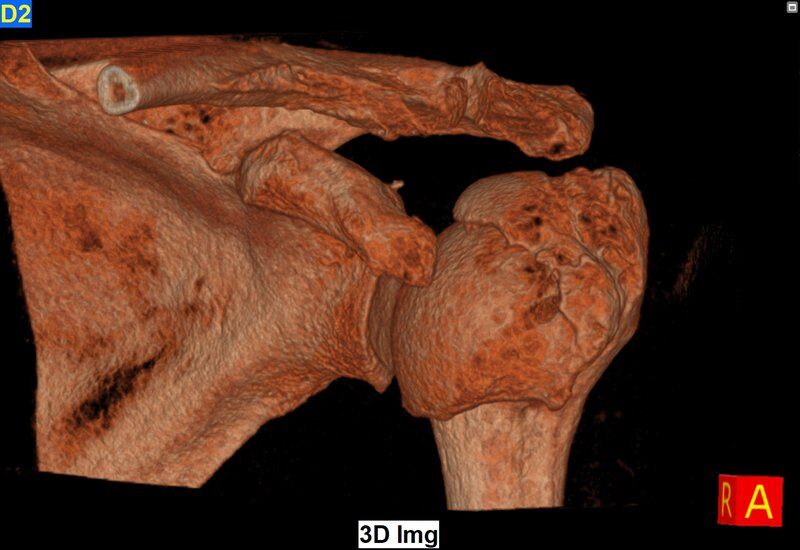

Newtom 7G ist das Multi-Scan Body DVT-System, das hochpräzise Diagnosen für eine Vielzahl von anatomischen Bezirken, einschließlich Wirbelsäule, Schulter und Hüfte, bietet.

Vom Mikrodetail bis hin zur Betrachtung von Makrostrukturen garantiert Newtom 7G dank einer Auflösung von bis zu 90 µm diagnostische Genauigkeit, ideal für die Analyse komplexester Strukturen wie Innenohr oder Mikro-Gelenkfrakturen.